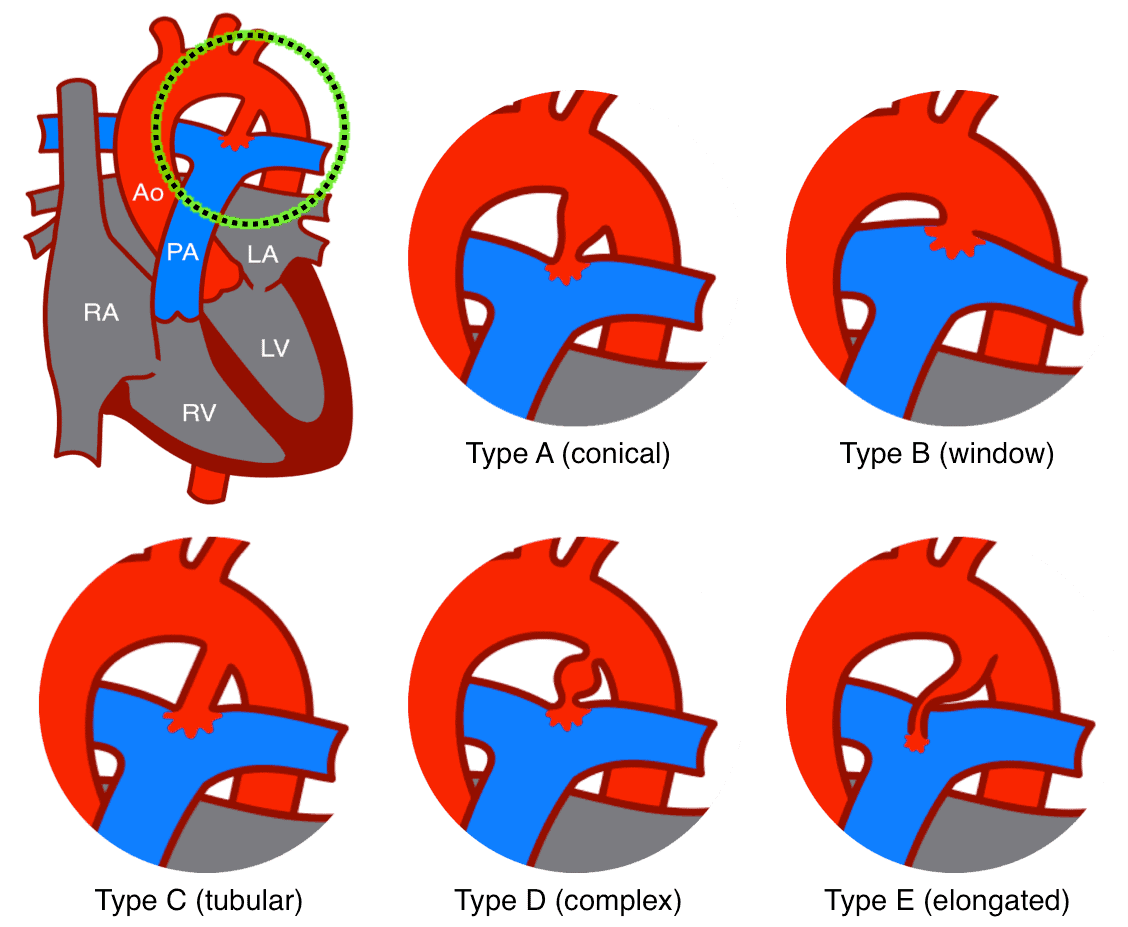

– Hình ảnh đảo ngược shunt có thể được xác định nếu nhìn thấy thuốc cản quang chảy từ bên phải của trái tim sang bên trái.3. Còn ống động mạch

– Ống động mạch nối liền nơi phân nhánh động mạch phổi và eo động mạch chủ, dưới chỗ xuất phát động mạch dưới đòn. Ống động mạch thông thương trong thời kỳ bào thai và đóng lại ngay sau sinh do tác dụng của sự sụt giảm Prostaglandin E2 và tăng nồng độ O2 máu nhờ động tác thở.

– Còn ống động mạch xảy ra trong 5-10% tất cả các bệnh tim bẩm sinh, thường gặp ở nữ hơn nam (nam/nữ = 1/3).

– Bệnh thường liên quan đến tiền sử mẹ nhiễm Rubella trong những tháng đầu thai nghén, một số trường hợp có yếu tố gia đình.

– Sinh lý bệnh:

+ Ống động mạch tồn tại trong quá trình phát triển của bào thai, tạo sự thông thương giữa động mạch chủ và động mạch phổi. Sau khi trẻ sinh ra đời bình thường ống động mạch đóng lại.

+ Nếu ống động mạch vẫn còn tồn tại gây luồng thông trái-phải gây quá tải tuần hoàn phổi, nhĩ trái và thất trái. Sự quá tải tuần hoàn phổi gây nên các biểu hiện hô hấp, tăng áp lực động mạch phổi và giãn động mạch phổi, giãn nhĩ trái và thất trái, giảm huyết áp tâm trương. Sự tăng áp lực động mạch phổi có thể xảy ra từ rất sớm.

+ Nếu kích thước của ống động mạch nhỏ, nguy cơ chủ yếu là viêm nội tâm mạc nhiễm trùng. Nếu kích thước ống động mạch lớn sẽ ảnh hưởng đến chức năng hô hấp của trẻ từ lúc sinh đến 12 tháng sau sinh và làm tăng áp lực động mạch phổi.

– Nếu ống động mạch nhỏ (< 3mm): hình ảnh X-quang bình thường

– Nếu ống động mạch lớn (> 4mm):

+ Trường hợp còn shunt trái – phải nhiều: dấu hiệu tăng gánh thất trái, buồng tim lớn (nhĩ trái, thất trái), cung động mạch phổi vồng và tăng tuần hoàn phổi chủ động.

+ Khi áp lực động mạch phổi tăng nhiều bóng tim bình thường, tuần hoàn phổi tăng đậm ở gốc, giảm nặng ở ngoại vi.

+ Quai động mạch chủ thường lớn do tăng cung lượng tim.4. Tứ chứng Fallot